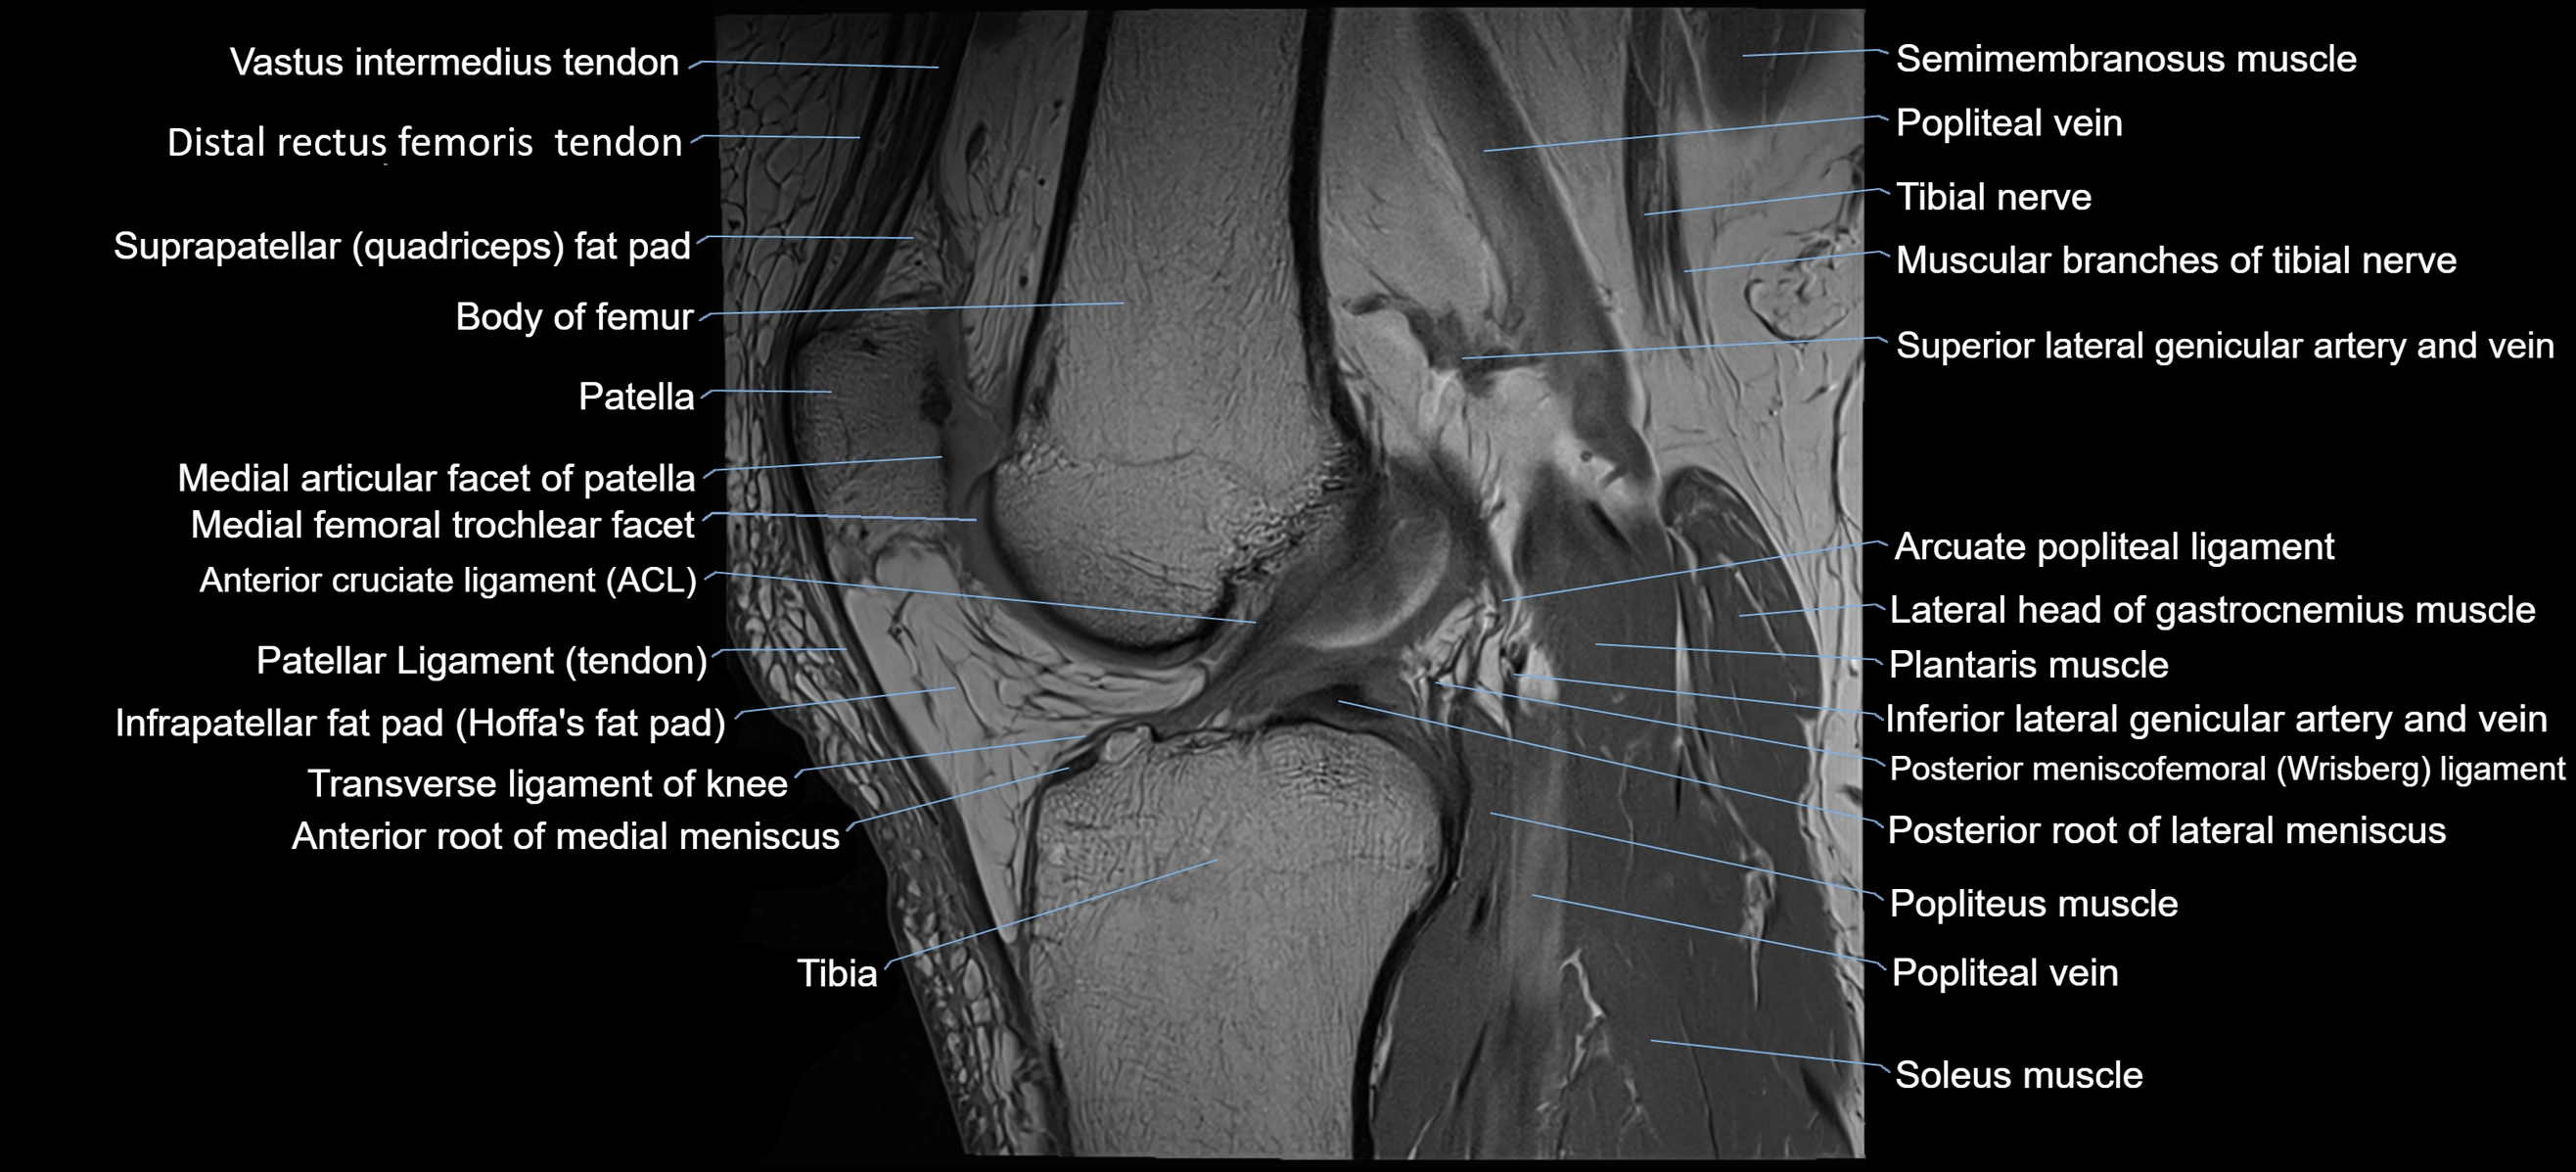

- Anterior cruciate ligament

- Anterior root of medial meniscus

- Arcuate popliteal ligament

- Body of femur

- Distal rectus femoris tendon

- Distal vastus intermedius tendon

- Infrapatellar fat pad

- Lateral head of gastrocnemius muscle

- Patella

- Patellar articular cartilage

- Patellar tendon (patellar ligament)

- Plantaris muscle

- Popliteal artery

- Popliteal vein

- Popliteus muscle

- Posterior meniscofemoral ligament

- Posterior root of lateral meniscus

- Prefemoral fat pad

- Semimembranosus muscle

- Soleus muscle

- Suprapatellar fat pad

- Tibia

- Tibial nerve

- Transverse ligament of knee